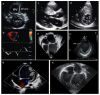

Cardiomyopathies are a heterogeneous group of myocardial diseases representing the first cause of heart transplantation in children. Diagnosing and classifying the different phenotypes can be challenging, particularly in this age group, where cardiomyopathies are often overlooked until the onset of severe symptoms. Cardiovascular imaging is crucial in the diagnostic pathway, from screening to classification and follow-up assessment. Several imaging modalities have been proven to be helpful in this field, with echocardiography undoubtedly representing the first imaging approach due to its low cost, lack of radiation, and wide availability. However, particularly in this clinical context, echocardiography may not be able to differentiate from cardiomyopathies with similar phenotypes and is often complemented with cardiovascular magnetic resonance. The latter allows a radiation-free differentiation between different phenotypes with unique myocardial tissue characterization, thus identifying the presence and extent of myocardial fibrosis. Nuclear imaging and computed tomography have a complementary role, although they are less used in daily clinical practice due to the concern related to the use of radiation in pediatric patients. However, these modalities may have some advantages in evaluating children with cardiomyopathies. This paper aims to review the strengths and limitations of each imaging modality in evaluating pediatric patients with suspected or known cardiomyopathies.